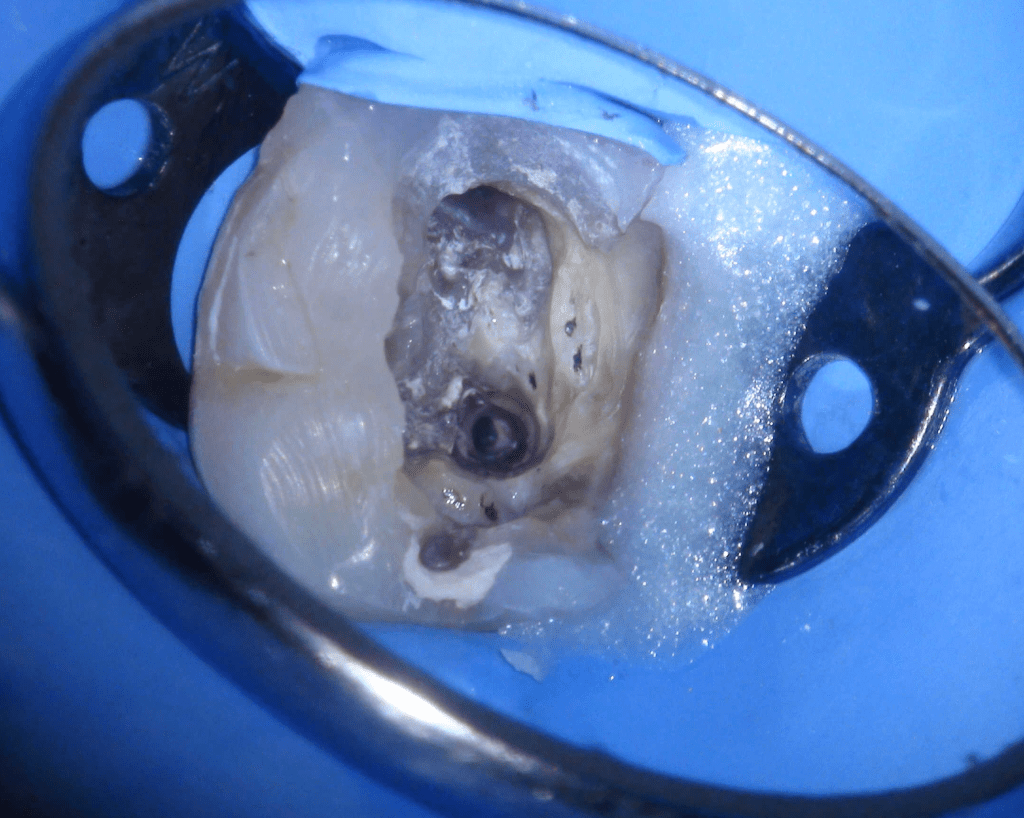

Reco preendo + 4 conductos molar superior